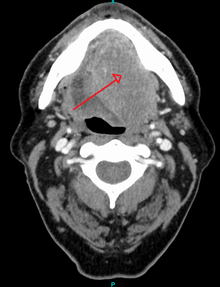

Head and neck cancer

Ninety percent[14] of cases of head and neck cancer (cancer of the mouth, nasal cavity, nasopharynx, throat and associated structures) are due to squamous cell carcinoma.